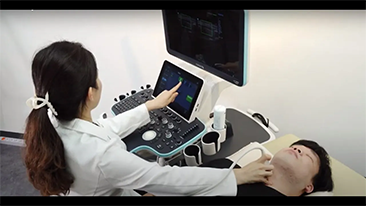

Solusi Pencitraan Umum Resona dari Mindray membantu para dokter mewujudkan diagnosis dan hasil pengobatan yang lebih akurat dan efisien melalui pemerik aplikasi subdivisi yang komprehensif dan alat bantu aplikasi klinis yang efisien.